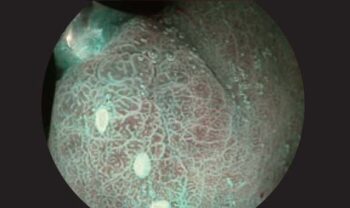

Олон гэрэлтүүлгийн горим: 4-LED гэрэлтүүлгийн эх үүсвэр нь олон спектрийн гэрэлтүүлгийг дэмжиж, хромоэндоскопийн горимд өндөр гэрэлтүүлгийг хангадаг.

Дүрс сайжруулалтын функцууд: Structure Enhancement, Edge Enhancement зэрэг функцууд нь эдийн бүтэц, ирмэгийг тодруулан, эмгэг өөрчлөлтүүдийг илрүүлэхэд тусалдаг.

SFI

VIST